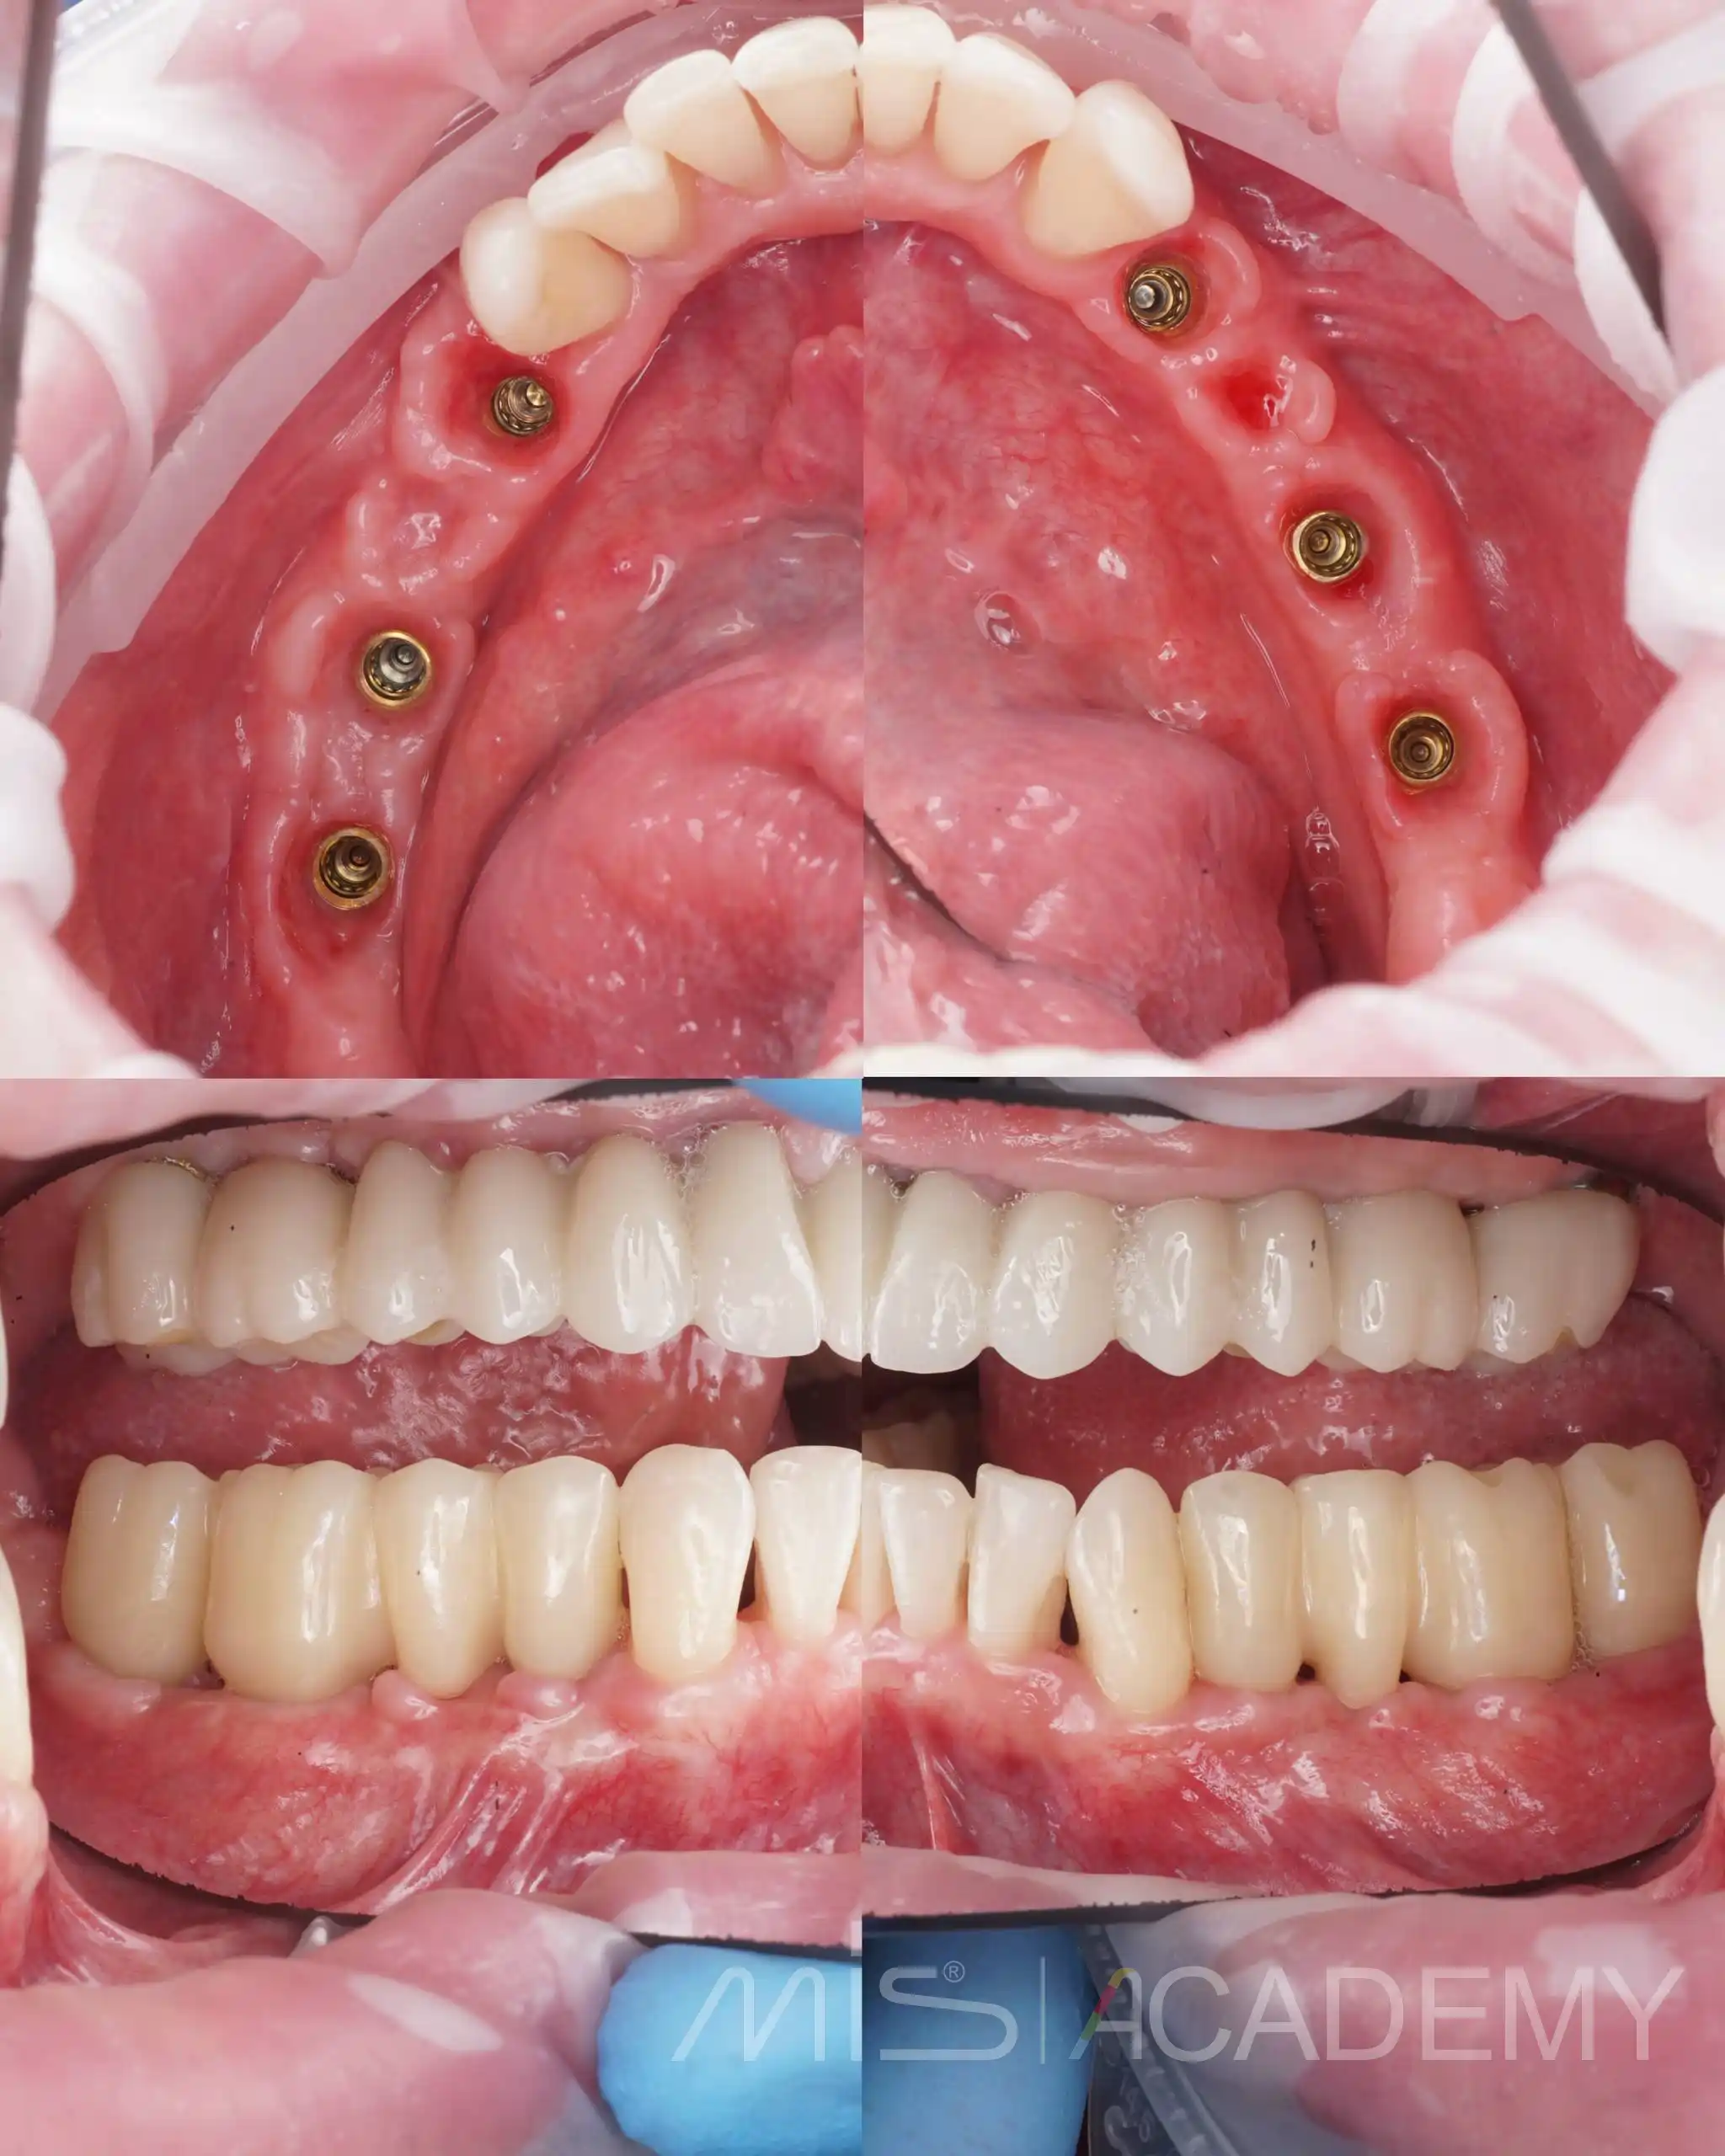

Первый этап верхняя челюсть:

— По навигационному накостному шаблону установили 6 имплантатов MIS C1.

— В дистальных отделах выполнены открытый и закрытый синуслифтинги под заглушки.

— Четыре имплантата в переднем отделе нагружены временной армированной конструкцией, разборная балка сварена непосредственно в полости рта, с уровня коннектов и угловых мультиюнитов.

— Во всех зонах имплантатов и понтиков выполнена пластика мягких тканей.

Через 1,5–2 месяца пациент передан Игорю Левушкину для завершения лечения ортопедическим этапом.